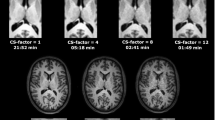

Figure 1 shows one slice of the 1H maps and 23Na images from the 3 scans of subject 1 after co-registration and masking. Figure 2 shows one selected slice of the 1H maps and 23Na images from the first scan of each subject after co-registration, using the maps from the subject 1 as a reference, and masking. Figure 3 shows the brain segmentation in gray matter (GM), white matter (WM), and cerebrospinal fluid (CSF) of scan 1 for subject 1. Table 1 summarizes the results of the statistical analysis for all tissues and all scans, where Meanall and SDall are the mean value and standard deviation calculated over all the data, Inter-Var is the inter-subject variation, Intra-Var is the mean intra-subject variation, CV is the mean coefficient of variation and ICC is the intra-class variation. Figure 1S in supplementary information shows images from subject 2 along the 3 axes.

Maps from the first scan acquired in all the subjects (after co-registration, using subject 1 as reference) with simultaneous 1H MRF/23Na MRI. The in-plane resolution is 1.5 × 1.5 mm2 for the proton images and 2.85 × 2.85 mm2 for the sodium image. Slice thickness is 3 mm for both nuclei. PD is normalized proton density and 23Na D is normalized sodium density.